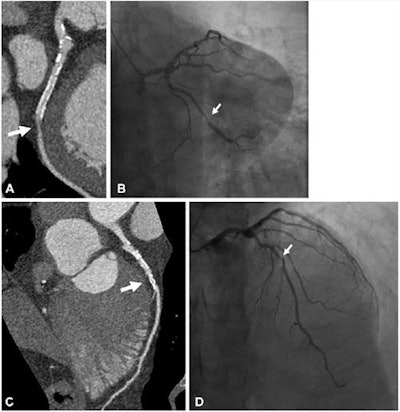

Example of a 61-year-old man with a history of myocardial infarction who was found at UHR-CT to have a severe (≥ 70%) stenosis in a large obtuse marginal branch of the left circumflex artery just distal to (A) a patent stent, which was confirmed at (B) invasive angiography. In addition, there was moderate disease noted by (C) ultrahigh-resolution CT in the left main and in the middle left anterior descending artery (50%-70% stenosis), which was underestimated compared with (D) invasive angiography (70% stenosis). Arrow points to corresponding stenoses. Images and caption courtesy of the RSNA.UHR-CT produced more image noise than conventional CT image reconstruction (50.9 versus 19.5), but even so, diagnostic confidence and image quality scores were high (4.3 and 4.1), the researchers found. When they compared the performance of ultrahigh-resolution CT to the gold standard of invasive angiography for evaluating stenosis, they found a sensitivity rate of 86% and specificity of 88%.